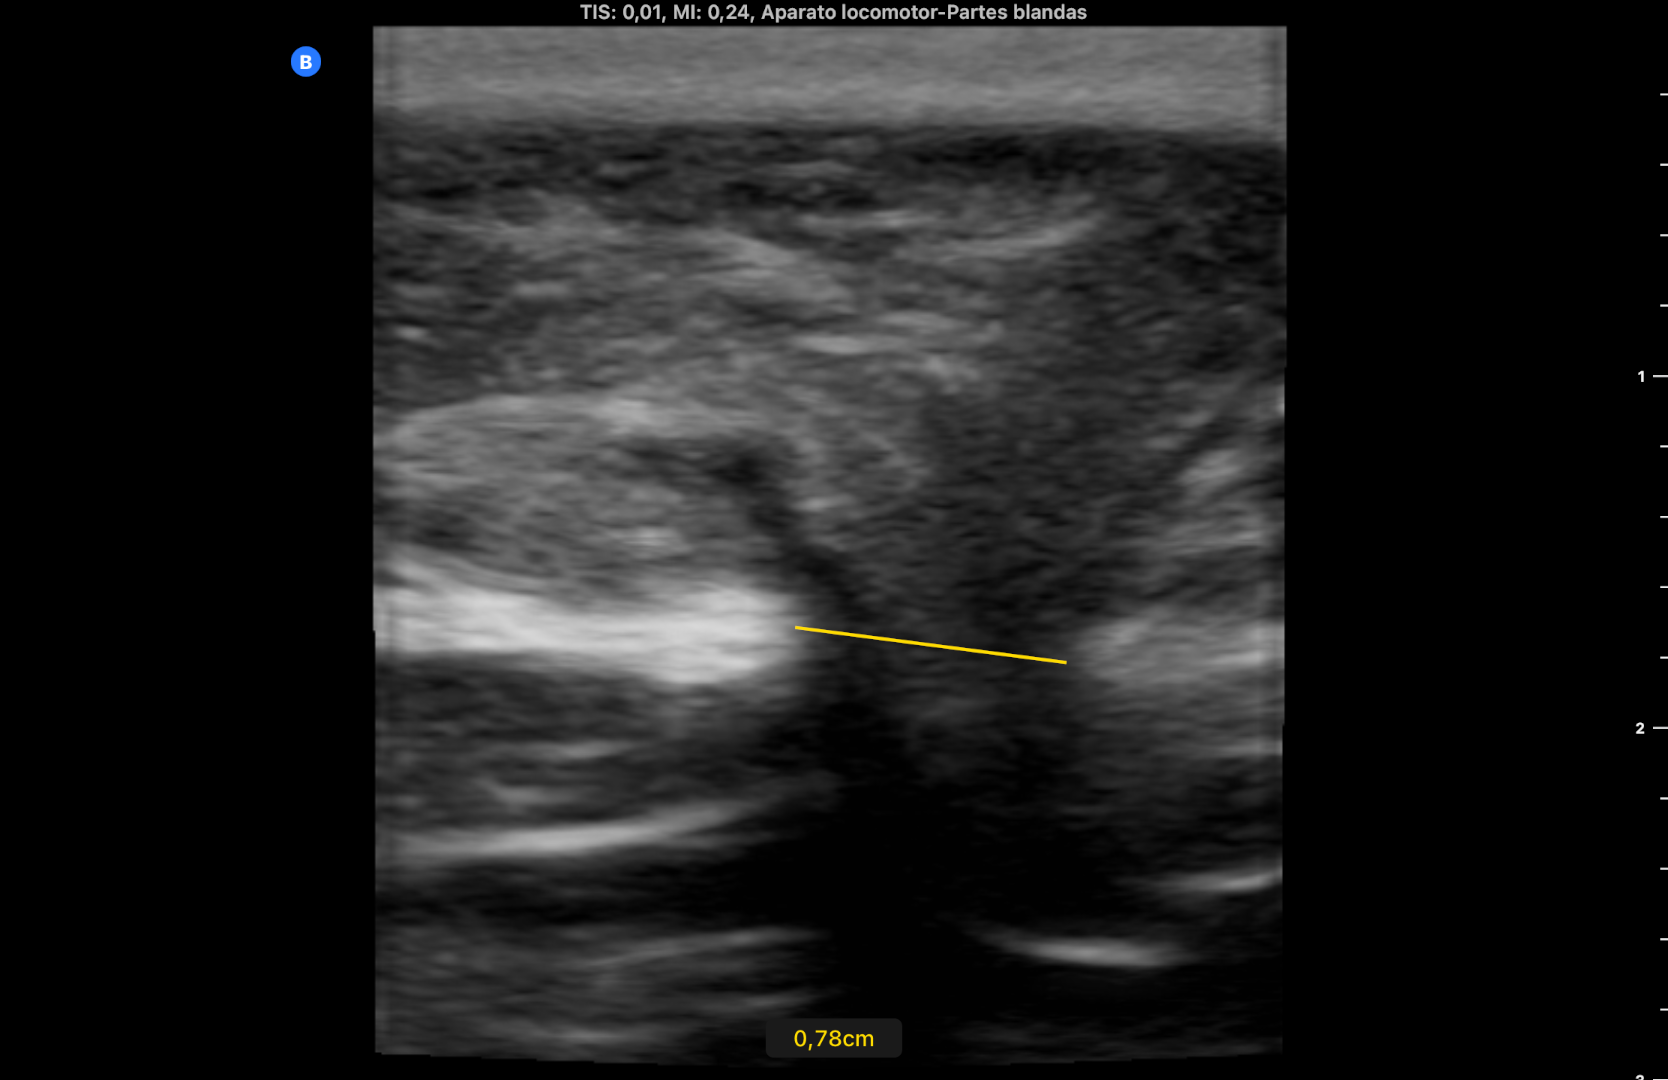

Se utiliza en la misma consulta una sonda portátil con preset de partes blandas, observando una imagen heterogénea redondeada, rodeada de líquido anecogénico a nivel subcutáneo que rompe la línea alba (imagen 1). Durante la exploración se comprime con la sonda en el lugar de la imagen consiguiendo la reducción de la misma y desapareciendo el dolor. La ecografía muestra entonces la discontinuidad de la línea alba con una pequeña protrusión de grasa (imagen 2) (se dispone de vídeos).

Se derivó al Servicio de Cirugía General por circuito preferente, advirtiendo de acudir a Urgencias si volvía a aparecer el bulto y el dolor. Se citó 6 días después persistiendo el orificio herniario de 7,8 mm sin extrusión de asa intestinal (imagen 3).